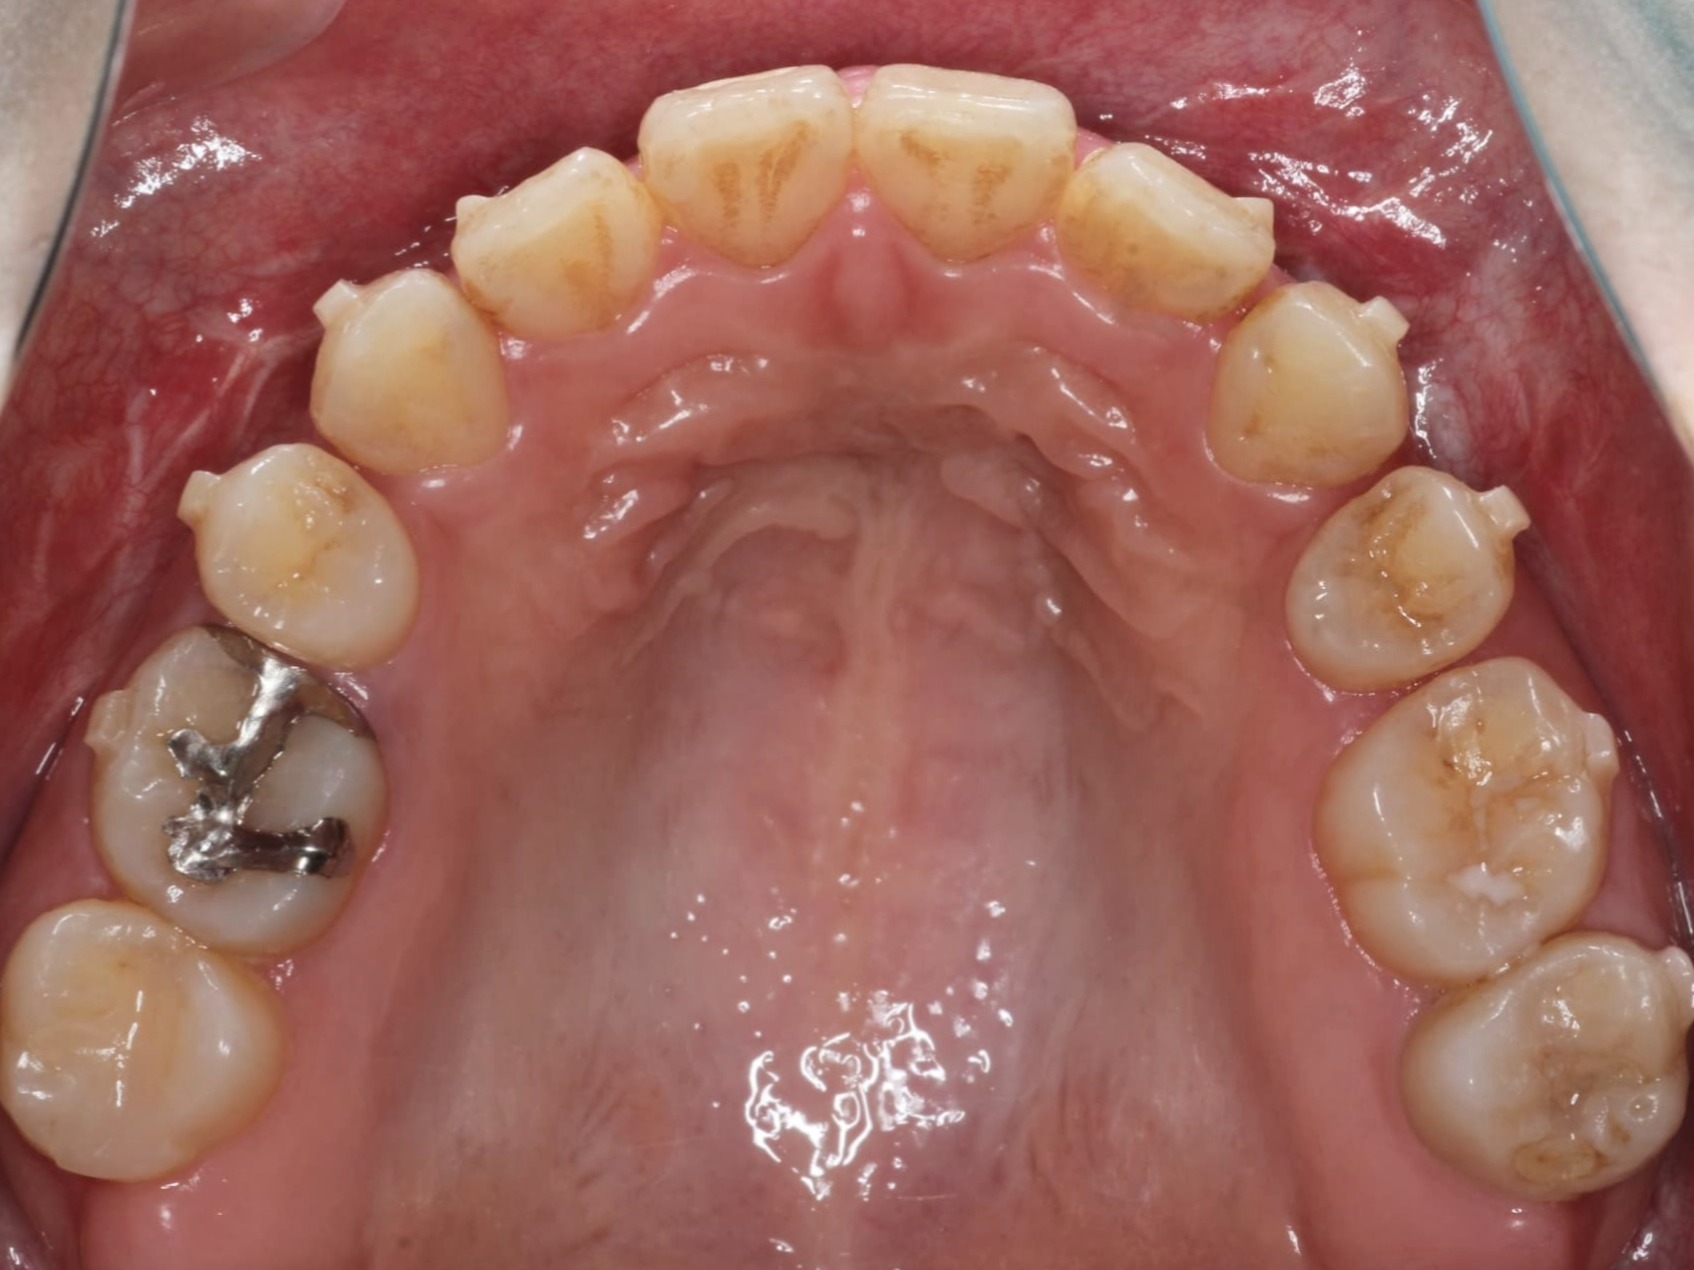

下顎前突、顔の左右差

症例概要 / Case details

- 治療名: インビザライン(両顎手術後矯正)

- 主訴: 下顎前突を治したい、顔の左右差もなくしたい

- 期間・回数: 9ヶ月 / 来院4回

- 費用の目安(自費・税込換算の目安): 1,200,000円(税込)

- リスクについて:使用時間に応じて歯の移動の結果が変わる場合があります。

治療内容の要点

下顎前突と正面から見た時のお顔の左右差をサージェーリーファーストにより改善し、その後の歯の軸や噛み合わせをマウスピース矯正にて整えていきました。

事前のシミュレーションを外科医の鶴木三郎先生とすり合わせをし、治療に進む前の段階で患者様に外科での骨の移動とその後の歯の移動についてご説明することで、最終ゴールがどうなるのかを知っていただいてから開始するため安心して治療を受けられている印象でした。まだ治療経過中ですが約8ヶ月である程度の位置まで歯が動いています。最後に口元をさらに下げる微調整の進行中です。